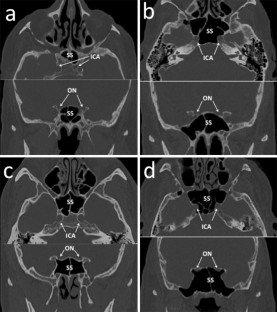

Relationship between sphenoid sinus volume and protrusion of internal carotid artery and optic nerve: a 3D segmentation study on maxillofacial CT-scans

Anatomy of sphenoid sinuses has acquired a growing importance with the diffusion of transsphenoidal surgical procedures. A common risk in these practices is the damage of internal carotid artery (ICA) and optic nerve (ON), which may protrude into the sphenoid air cavities. This study aims at analysing the relationships between sphenoid sinuses volume and protrusion of ICA and ON.

260 head CT-scans were retrospectively analysed (equally divided among males and females, age range 20–92 years). Volume was segmented through ITK-SNAP software. In addition, the subjects were classified into four groups: no protrusion of any structure (group 1), protrusion of ICA (group 2), protrusion of ON (group 3), protrusion of both ICA and ON (group 4). Possible statistically significant differences in prevalence of the four groups according to gender were assessed through Chi-squared test (p < 0.05). Differences in volume between the four groups were assessed through one-way ANOVA test (p < 0.05), separately for males and females.

Group 1 was the most frequent (40.0%), followed by group 4 (27.7%) and group 2 (18.5%), without any difference according to gender. For what concerns volume, cases of ICA and concomitant ICA + ON protrusion had significantly larger sinuses, whereas isolated ON protrusion did not modify sinus volume.

Results show that protrusion of ICA is positively related with the volume of sphenoid sinuses, whereas the same relation was not verified for ON: surgeons should accurately consider possible ON protrusion in each case, as it may occur independently from sphenoid sinuses volume.